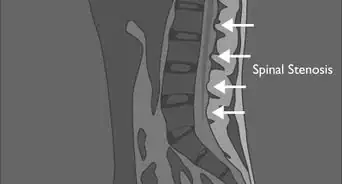

2See a medical specialist. If you have a positive scoliosis screening or have reason to believe your spine is somehow abnormal, then see a medical specialist. An orthopedic surgeon will carefully examine your spine and likely take X-rays to better understand your problem. The specialist will look for relatively common spinal pathologies such as osteoarthritis, osteoporosis and herniated discs — all of which can lead to abnormal spinal curvature and biomechanics.[15]

- Specialists may also use CT scans, MRI, bone scans or more sophisticated X-rays to further diagnose your spinal condition.